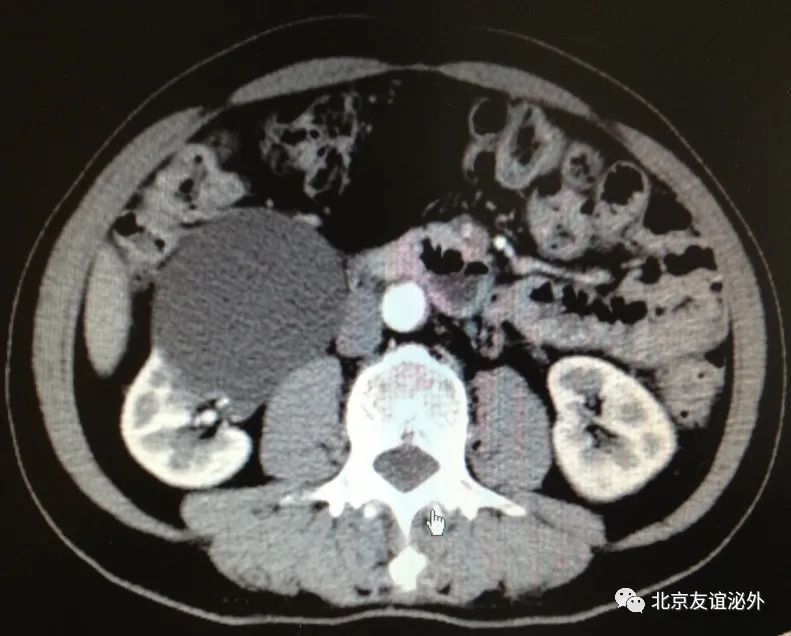

图1. Bosniak I级良性囊肿,是临床上最常见的囊肿